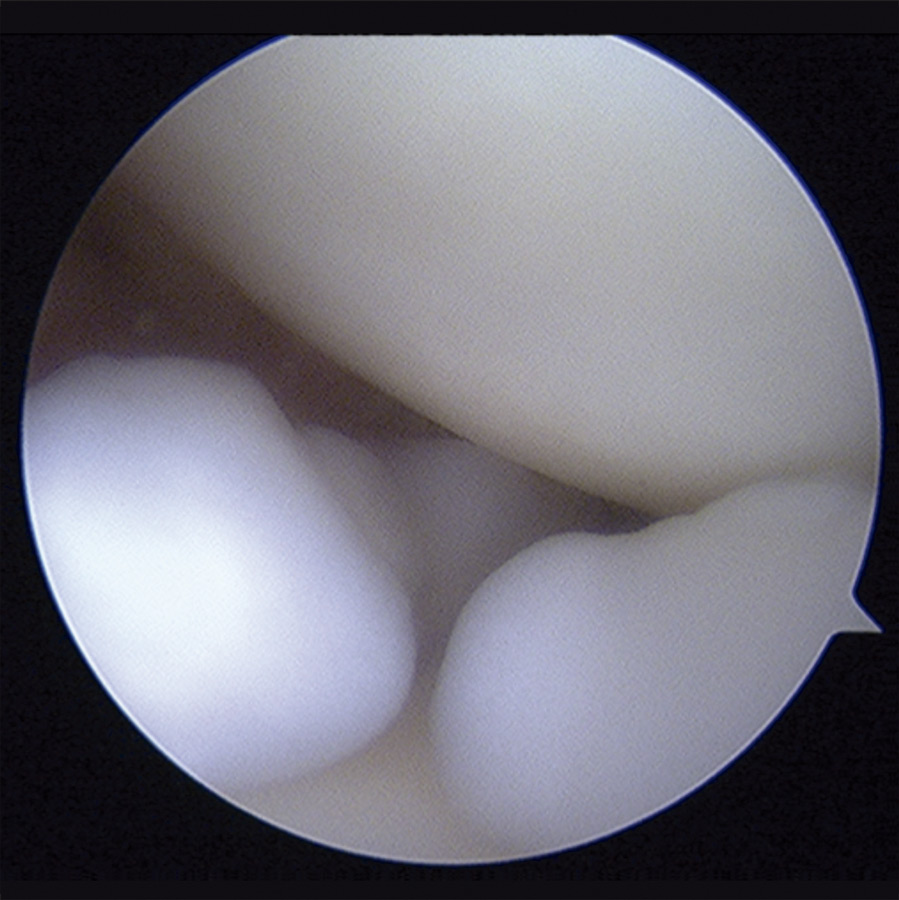

Con el diagnóstico de condromatosis sinovial de hombro derecho se procedió a la realización de una artroscopia, viendo múltiples cuerpos libres intraarticulares, la mayoría de ellos de consistencia cartilaginosa (Figuras 3 y 4) y se procedió a su extracción por vía artroscópica (Figura 5). Tras la cirugía, se remitió a la paciente a recuperación funcional, presentando una buena evolución clínica. La paciente se encuentra asintomática en el momento actual, presentando un balance articular completo.

Figura 3. Imagen artroscópica: cuerpos libres en condromatosis sinovial.